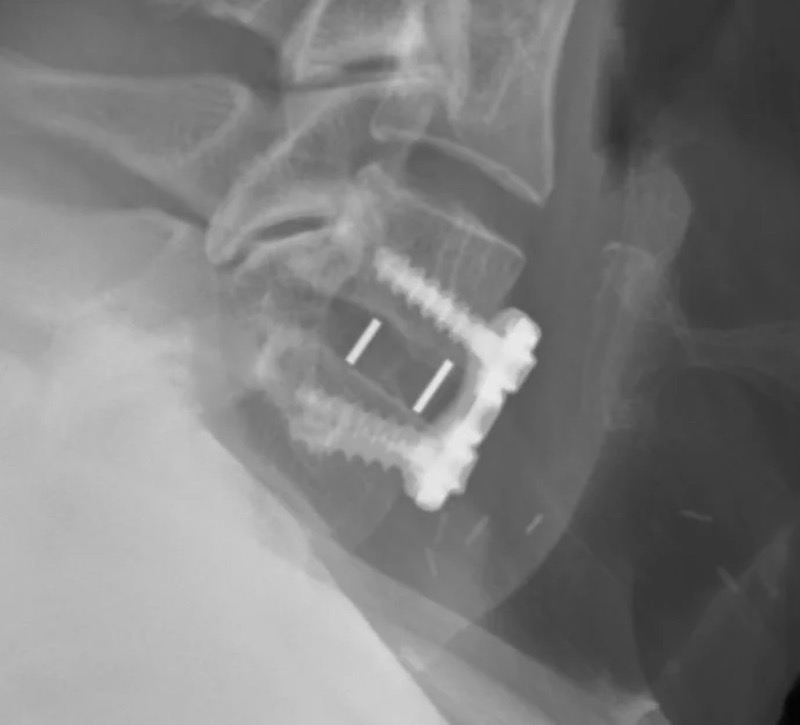

Cohere Cervical Porous PEEK ACDF Spacer

Cohere Cervical by Nuvasive (Globus) is a porous PEEK implant used for anterior cervical discectomy and fusion procedure. The porous surface structure is designed to promote bone ingrowth while maintaining the inherent biomechanical and imaging properties of PEEK.

• Radiolucent porous PEEK for bone ingrowth

• Footprint (LxW):

• 12 x 14 mm

• 14 x 16 mm

• Height:

• 6-10 mm

• Lordosis:

• 7 degree